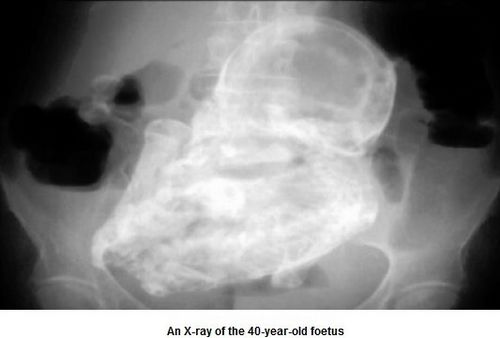

中新网12月13日电 据外媒报道,哥伦比亚首都波哥大一名82岁老妇,8日因腹痛就医,医师惊讶地发现,造成她腹痛的原因,竟是一个已形成40年的“石胎”。

起初医师以为老妇是因为寄生虫或是胆结石导致腹痛,但察觉老妇腹部有异状,经X光检验才查出老妇体内居然有一个胎儿,而且胎儿在老妇体内长达40年,由于胚胎未在子宫里发育,移到患者的腹腔,导致胚胎无法正常生长,钙化后形成“石胎”。